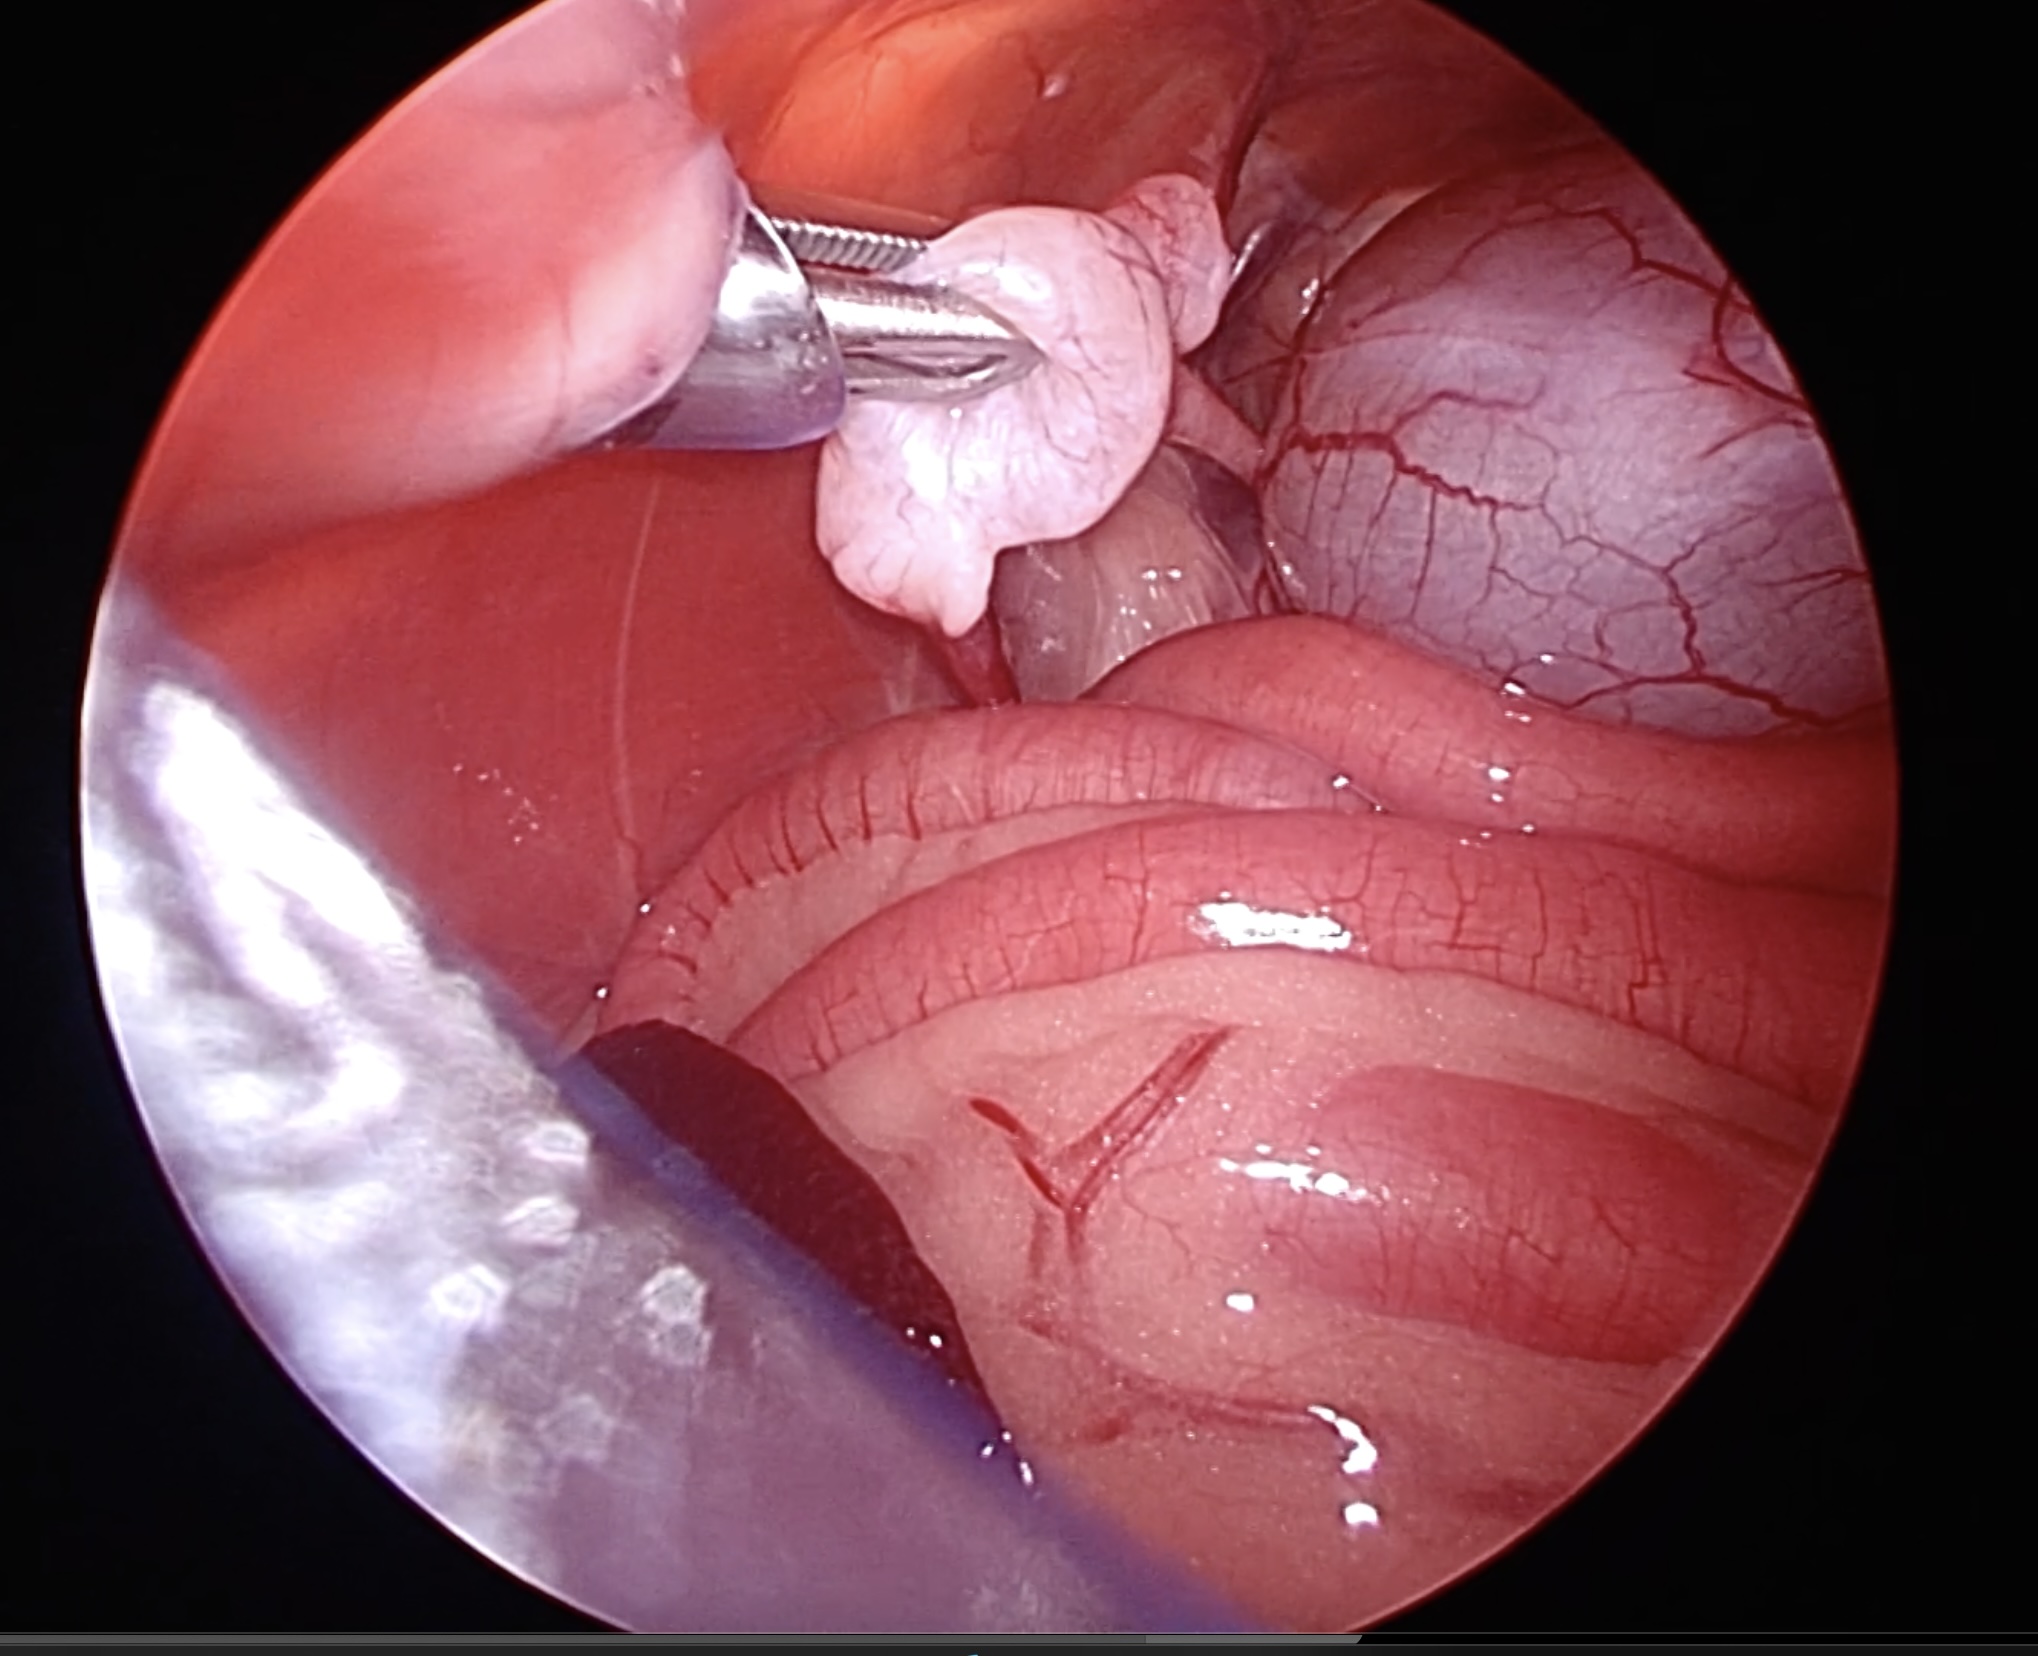

体外に出ずに膀胱の横にとどまっている精巣(右精巣)

左横腹からポートを設置し、精巣をつまみ上げます

右横腹びポートから電気メスのような止血切断デバイスを用いて、精巣の血管を処理、切断します